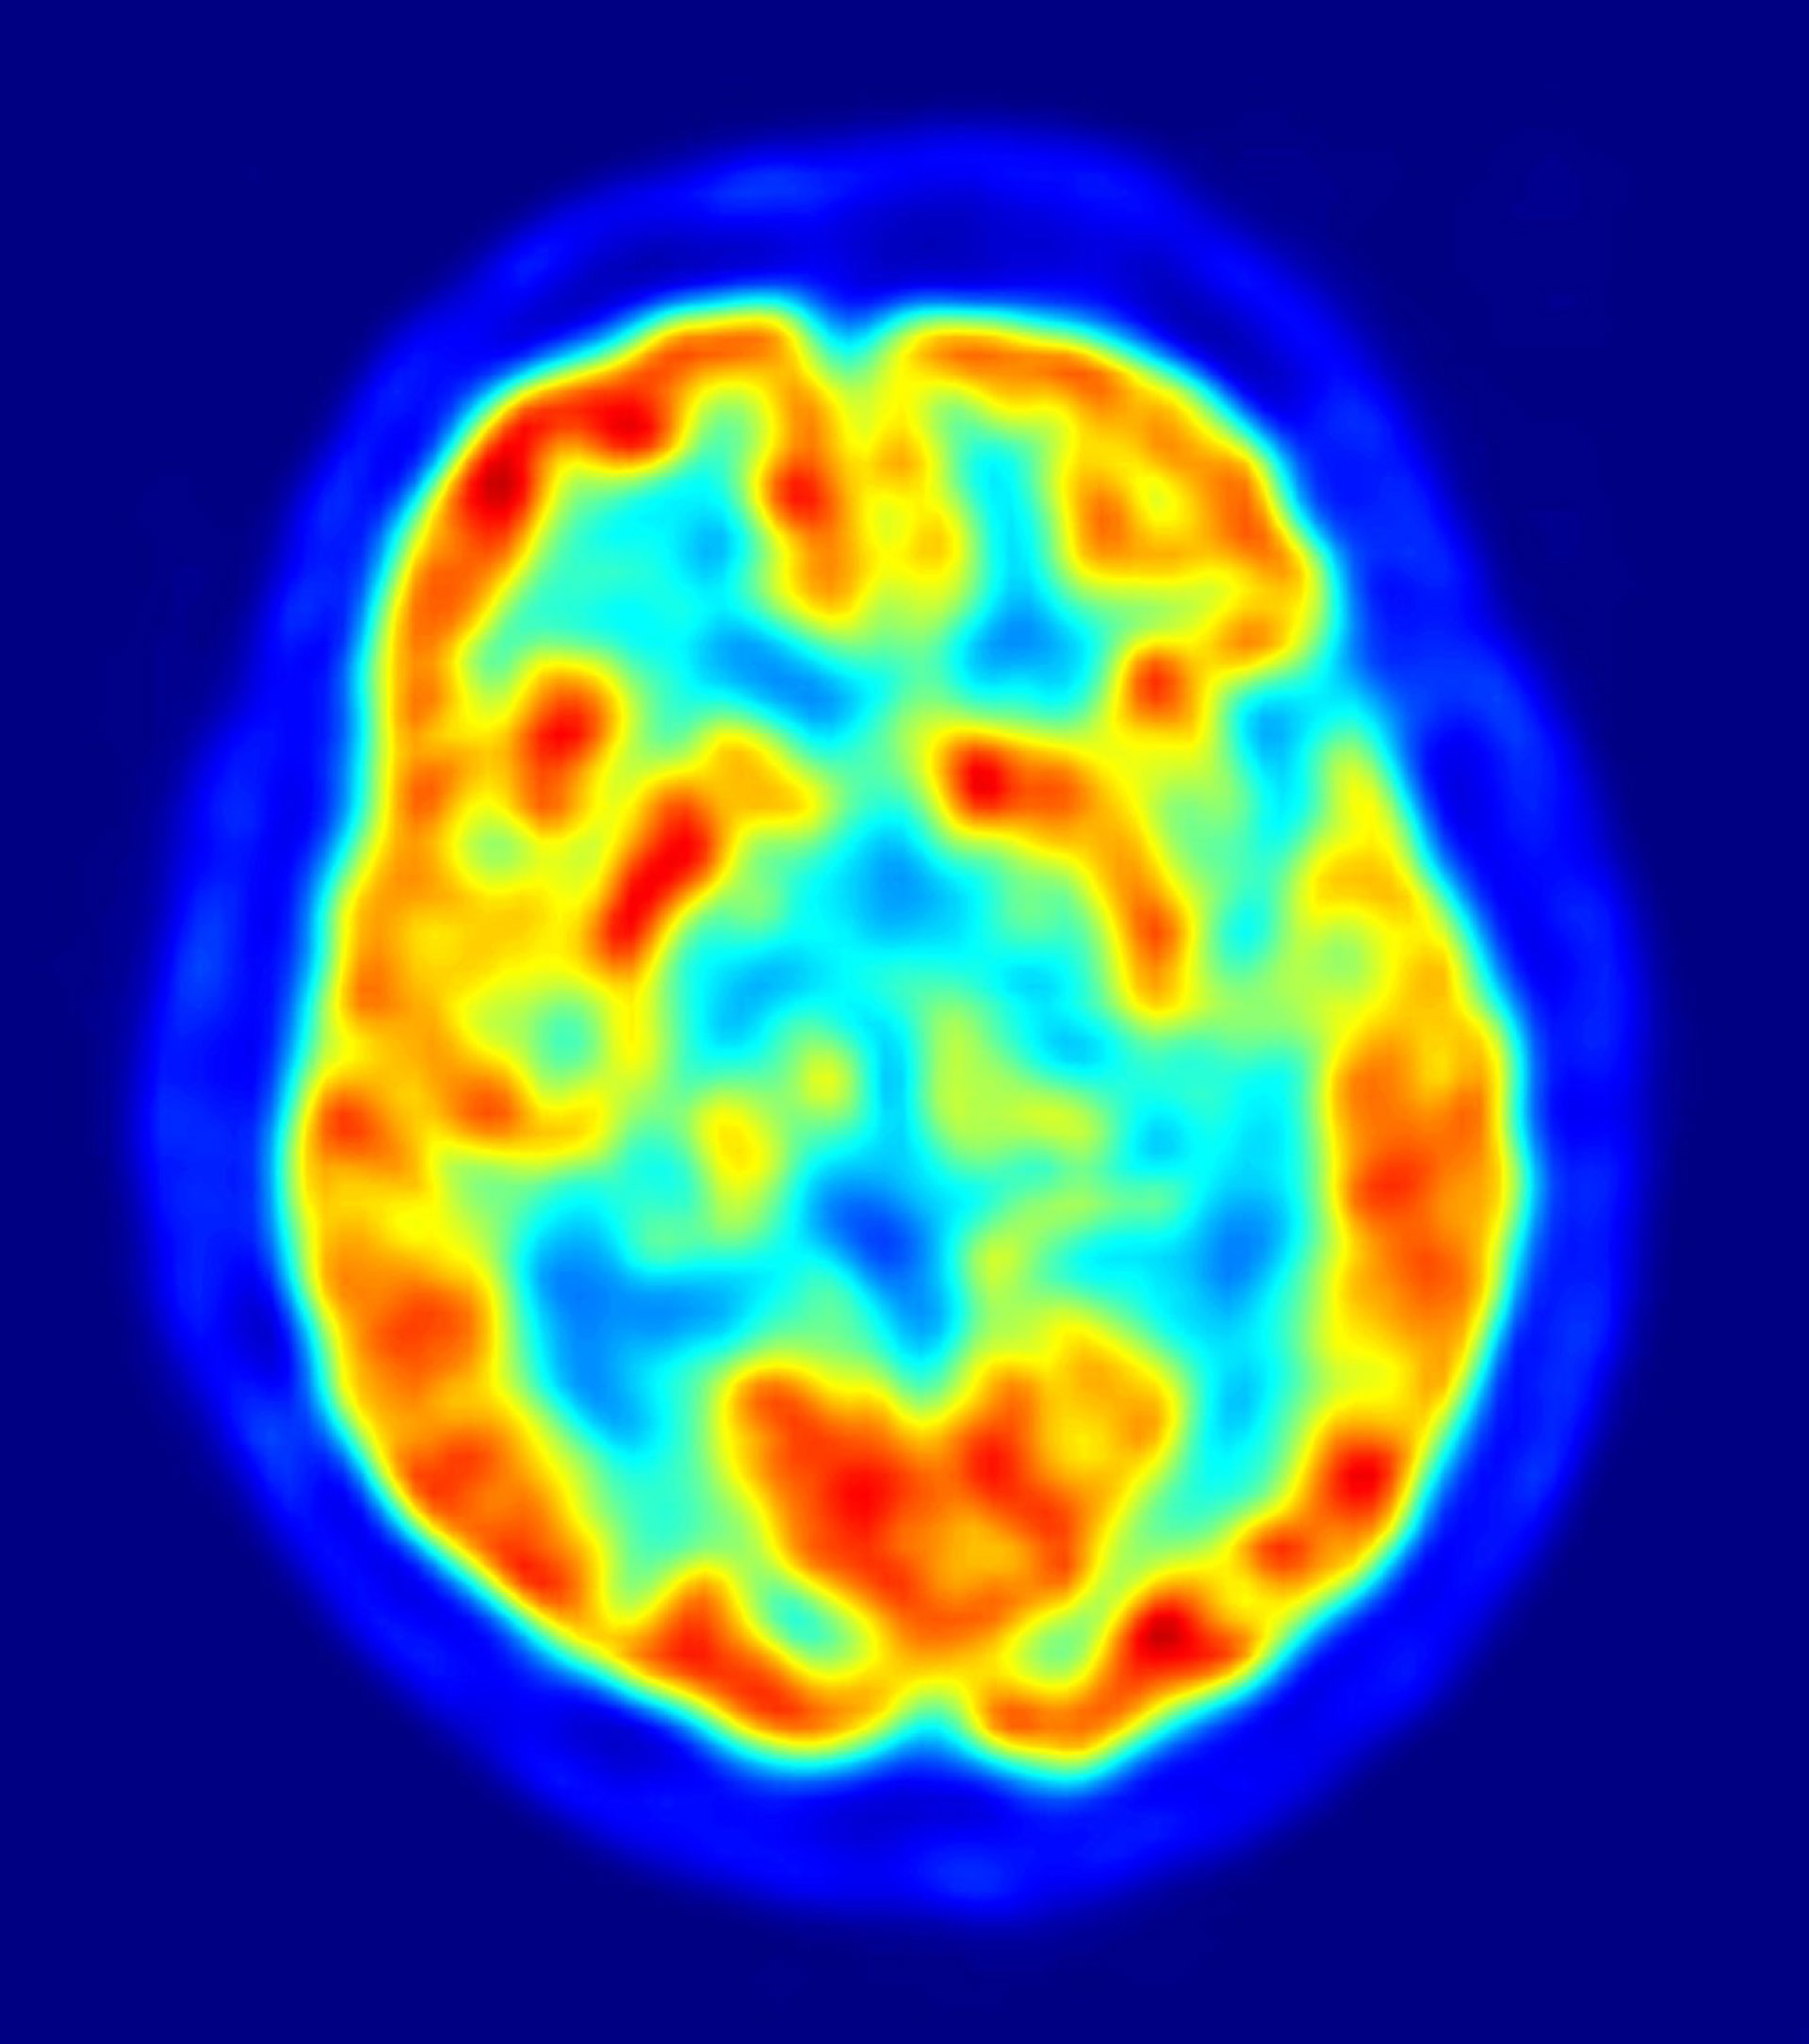

cerebro, recurso, neuronas

La enfermedad de Huntington es una enfermedad mortal, caracterizada por movimientos involuntarios de las extremidades, y alteraciones cognitivas y psiquiátricas. La enfermedad surge a partir de mutaciones en el gen de la huntingtina, que provoca que fragmentos de proteínas tóxicas se acumulen en el cerebro.

Anteriores esfuerzos preclínicos para bloquear la producción de la proteína huntingtina mutada no han conseguido resultados, ya que se han dirigido solo a una pequeña porción del cerebro. "Debido a que el gen de la huntingtina se expresa ampliamente, es probable que se requiera apuntar a múltiples regiones del cerebro para lograr un tratamiento efectivo", añade Cleveland.

En el nuevo estudio, Cleveland y su equipo redujeron los niveles de huntingtina mutada en todas las regiones del cerebro, en varios modelos de ratón y primates no humanos, de la enfermedad de Huntington. Los científicos lograron una reducción duradera de los niveles de huntingtina, a través de una infusión de cadenas simples de ADN -llamadas oligonucleótidos antisentido- que se unen de forma selectiva a las moléculas, degradando aquellas que contienen instrucciones para crear la proteína mutante.